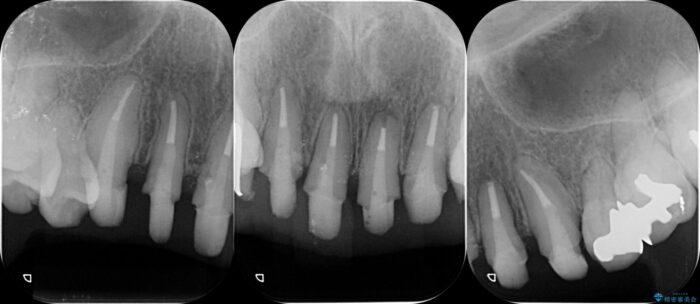

治療後について

治療には歯肉を成熟させる期間を含めて約8ヶ月間要しましたが、出血や違和感のない歯ぐきとなり大変ご満足いただけました。